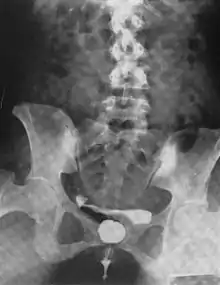

A urethral diverticulum seen on urethrogram

Another view of a urethral diverticulum seen on urethrogram

Urethral diverticulum is often an incidental finding.[2] It can be diagnosed using magnetic resonance imaging and/or micturating cystourethrography.[1] Other studies that can be used to diagnose urethral diverticulum include intravenous urography, urethroscopy, and/or ultrasound. Conditions that should be distinguished from urethral diverticulum in a differential diagnosis include overactive bladder, Gartner's duct cyst, Gartner's duct abscess, ectopic caeco-ureterocele, interstitial cystitis, pelvic inflammatory disease, endometriosis, and cancer.[3]